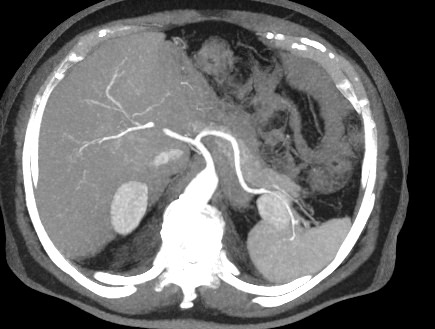

Печеночная ткань имеет обильное кровоснабжение, поэтому часто ультразвуковая диагностика заболеваний печени затруднена. Одним из наиболее информативных методов диагностики является мультиспиральная КТ печени, которая может проводиться в стандартном режиме и с внутривенным болюсным контрастированием. Введение йодсодержащего контрастного вещества значительно повышает диагностическую ценность компьютерной томографии и позволяет, в частности, выявить злокачественное образование на ранней стадии, отличить доброкачественный процесс от злокачественного, визуализировать изменения внутрипеченочных желчных протоков и многие другие патологические процессы.

В нашей клинике сканирование печени выполняется на современных компьютерных томографах экспертного класса TOSHIBA AQUILION, которые производят послойное сканирование исследуемого органа с последующей цифровой обработкой полученных данных для создания трехмерных изображений печени высокого качества и контрастности. Увеличенное количество детекторов, вмонтированных в аппараты, обеспечивает быстрое время исследования и пониженные дозы рентгеновского излучения, получаемого пациентом.